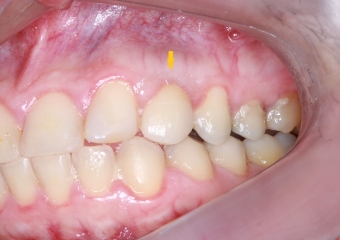

Janeiro de 2016, Controle de 3 anos